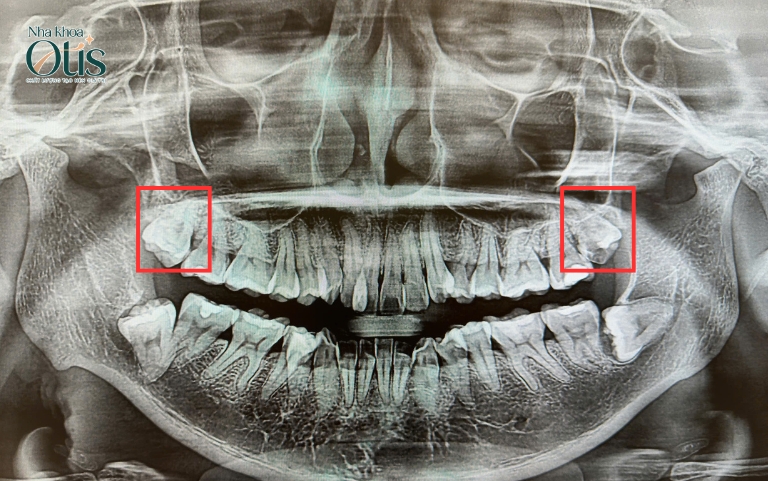

Thông thường, hàm trên không có dây thần kinh, nên trong nhiều trường hợp răng khôn mọc thẳng, khách hàng không cần lo lắng nhổ răng khôn ảnh hưởng dây thần kinh. Tuy nhiên, nếu răng khôn mọc lệch, mọc ngầm, đâm vào răng số 7 khiến đau nhức âm ỉ, bạn nên nhổ răng khôn sớm để tránh ảnh hưởng đến toàn hàm.

Khi răng khôn hàm trên mọc nghiêng vào răng số 7 dễ tạo khe giắt thức ăn. Khi khu vực này khó vệ sinh, răng số 7 có nguy cơ bị sâu hoặc viêm nha chu. Nếu phát hiện dấu hiệu ê buốt, hôi miệng, hoặc sâu mặt bên trong răng số 7, bác sĩ khuyến nghị nên nhổ răng khôn để bảo tồn răng 7 – răng hàm chính.

Ngoài ra, trong trường hợp răng khôn đối diện ở hàm dưới đã nhổ, bạn cũng nên nhổ răng khôn hàm trên. Vì khi không còn điểm chặn, răng khôn hàm trên có thể trồi xuống thấp hơn vị trí bình thường, gây cọ xát vào nướu dưới hoặc làm mất cân bằng khớp cắn. Nhổ bỏ trong trường hợp này giúp ổn định lực nhai và ngăn ngừa đau khớp thái dương hàm.